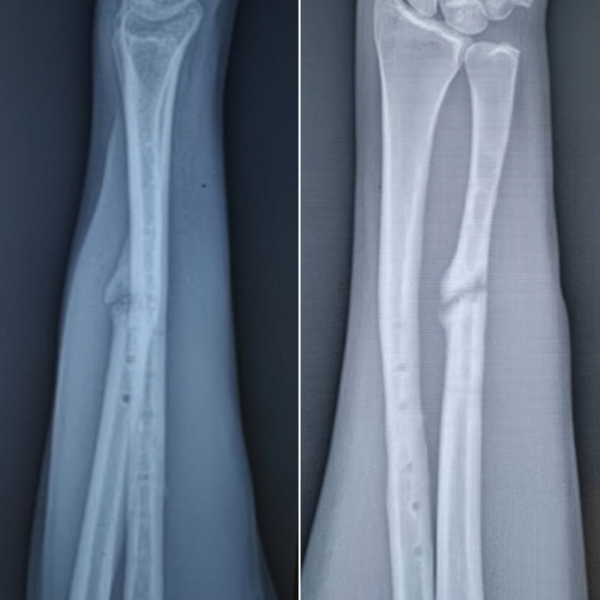

Prezentăm cazul unei paciente de 37 de ani, care s-a prezentat în serviciul nostru cu o recidivă a unei fracturi a ulnei. Cu aproximativ 1 an înainte a suferit o fractură deschisă a ambelor oase ale antebrațului prin cădere de la înălțime, care a fost tratată prin reducere deschisă și fixare internă cu plăci DCP. Tot la momentul accidentului a prezentat și o leziune a nervului ulnar, care a necesitat explorare și grefare, intervenție efectuată la interval de 6 săptămâni după traumatismul inițial. Plăcile au fost ulterior extrase din cauza proeminenței materialului de osteosinteză, iar la 6 săptămâni după această intervenție a suferit o refracturare a ulnei în urma unui nou traumatism. Leziunea a fost tratată nonoperator, după 9 luni confirmându-se diagnosticul de pseudartroză (Imaginea 1). Pacienta acuza durere și limitarea funcțională a antebrațului cu reducerea supinației.

Imaginea 1. Pseudartroza ulnei